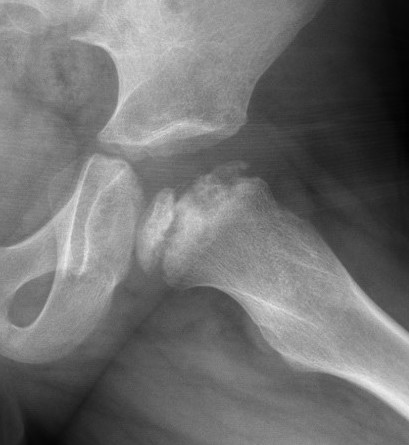

Femoral head reduction osteotomy (FHRO)

Concept

Misshapen femoral head

Open surgical dislocation

- remove central necrotic area femoral head

- rreposition lateral femoral head to medial femoral head

Results

Eltayeby et al J Pediatr Orthop B 2024

- 22 severe Perthes treated with FHRO

- 23% poor outcomes